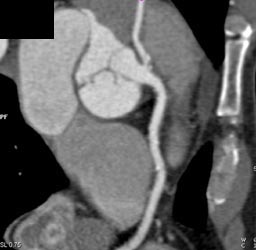

Left Main Off Right Coronary Artery